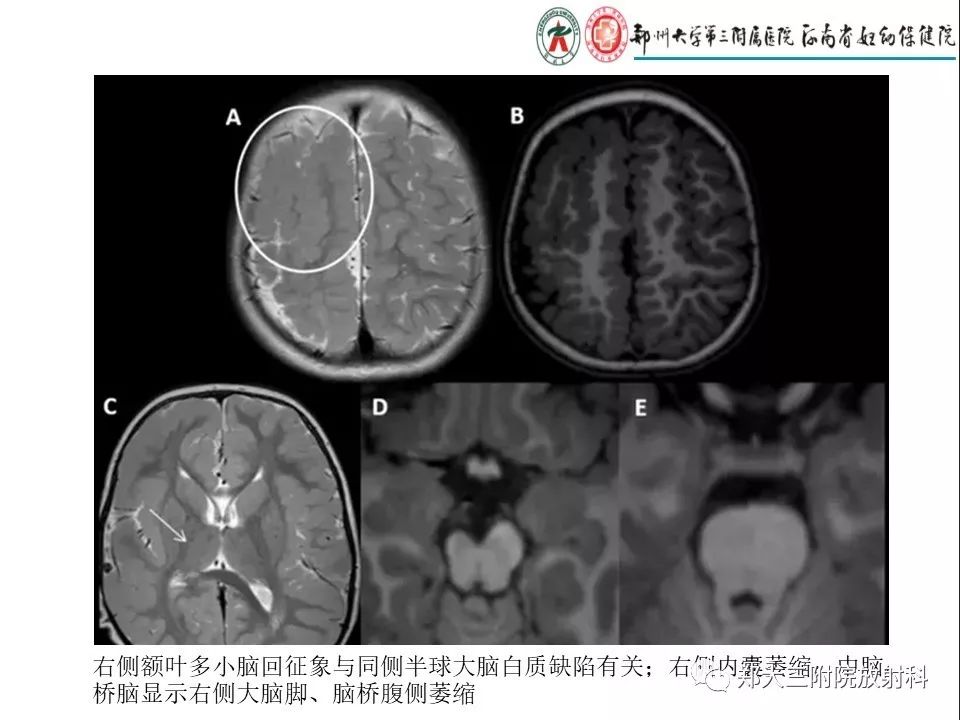

【PPT】多小脑回畸形的影像表现